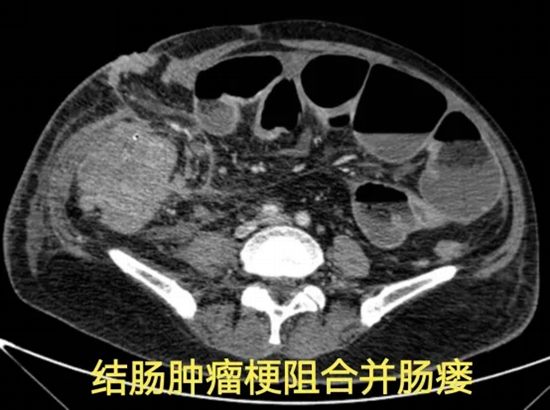

病情简述:56岁女性,两次腹膜后手术后出现降结肠瘘。

诊疗破局:按传统疗法,需先做结肠造口(挂粪袋),等半年后再做二次手术还纳。为减轻患者痛苦,团队制定“清创、控感、一期修复”三步法,实施腹腔镜下瘘切除+一期结肠端端吻合术。术后一周患者正常进食,免去了半年造口之苦。